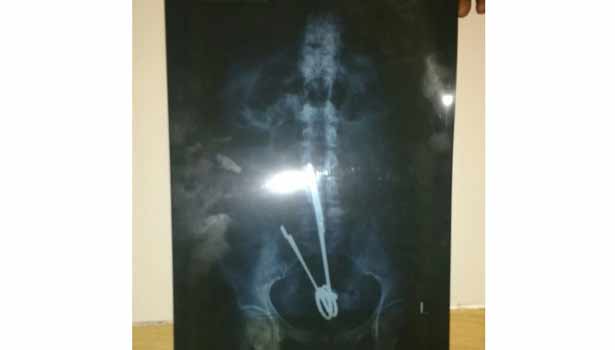

18 ஆண்டாக பெண் வயிற்றில் இருந்து கத்திரிகோல் அகற்றம்: ஸ்டான்லி ஆஸ்பத்திரியில் ஆபரேஷன்..!!

பெண் வயிற்றில் இருந்த கத்திரிகோல் 18 ஆண்டுகளுக்கு பிறகு அகற்றப்பட்டது

கடந்த 18 ஆண்டுக்கு முன்பு சரோஜா ஒரு அரசு ஆஸ்பத்திரியில் அப்பண் டீஸ் ஆபரேஷன் செய்து கொண்டார்.

ஆபரேஷன் செய்தபோது வயிற்றில் தவறுதலாக கத்திரிக்கோலை வைத்து தைத்து விட்டனர்.

2014–ம் ஆண்டு ஒரு விபத்தில் சிக்கிய சரோஜாவுக்கு ஸ்கேன் செய்து பார்க்கப்பட்ட போது அவரது வயிற்றில் கத்திரிக்கோல் இருப்பது தெரிந்தது.

இந்த நிலையில் நேற்று வயிற்று வலியால் சரோஜா துடித்தார். உடனே அவரை ஸ்டான்லி ஆஸ்பத்திரியில் சேர்த்தனர். அவருக்கு ஸ்கேன் செய்தபோது கத்திரிக்கோல் இருப்பதை கண்டு டாக்டர்கள் அதிர்ச்சி அடைந்தனர்.

உடனே சரோஜாவுக்கு ஆபரேஷன் செய்யப்பட்டது. 18 ஆண்டாக அவரது வயிற்றில் இருந்த கத்திரிக்கோல் அகற்றப்பட்டது. அவருக்கு தீவிர சிகிச்சை அளிக்கப்பட்டு வருகிறது.